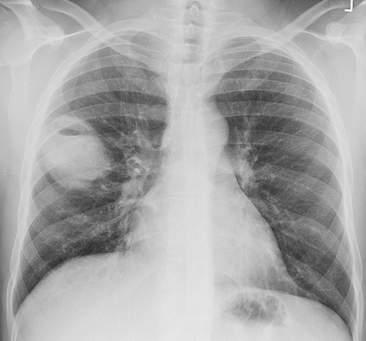

- Chụp X-quang phổi/ngực: Giúp phát hiện các bệnh lý như viêm phổi, lao phổi, ung thư phổi, tràn dịch màng phổi, và các vấn đề về tim.

- Bệnh lý phổi và lồng ngực: Hình ảnh X-quang ngực giúp phát hiện hiệu quả viêm phổi, tràn dịch màng phổi, lao, hoặc các dấu hiệu bất thường về kích thước tim.